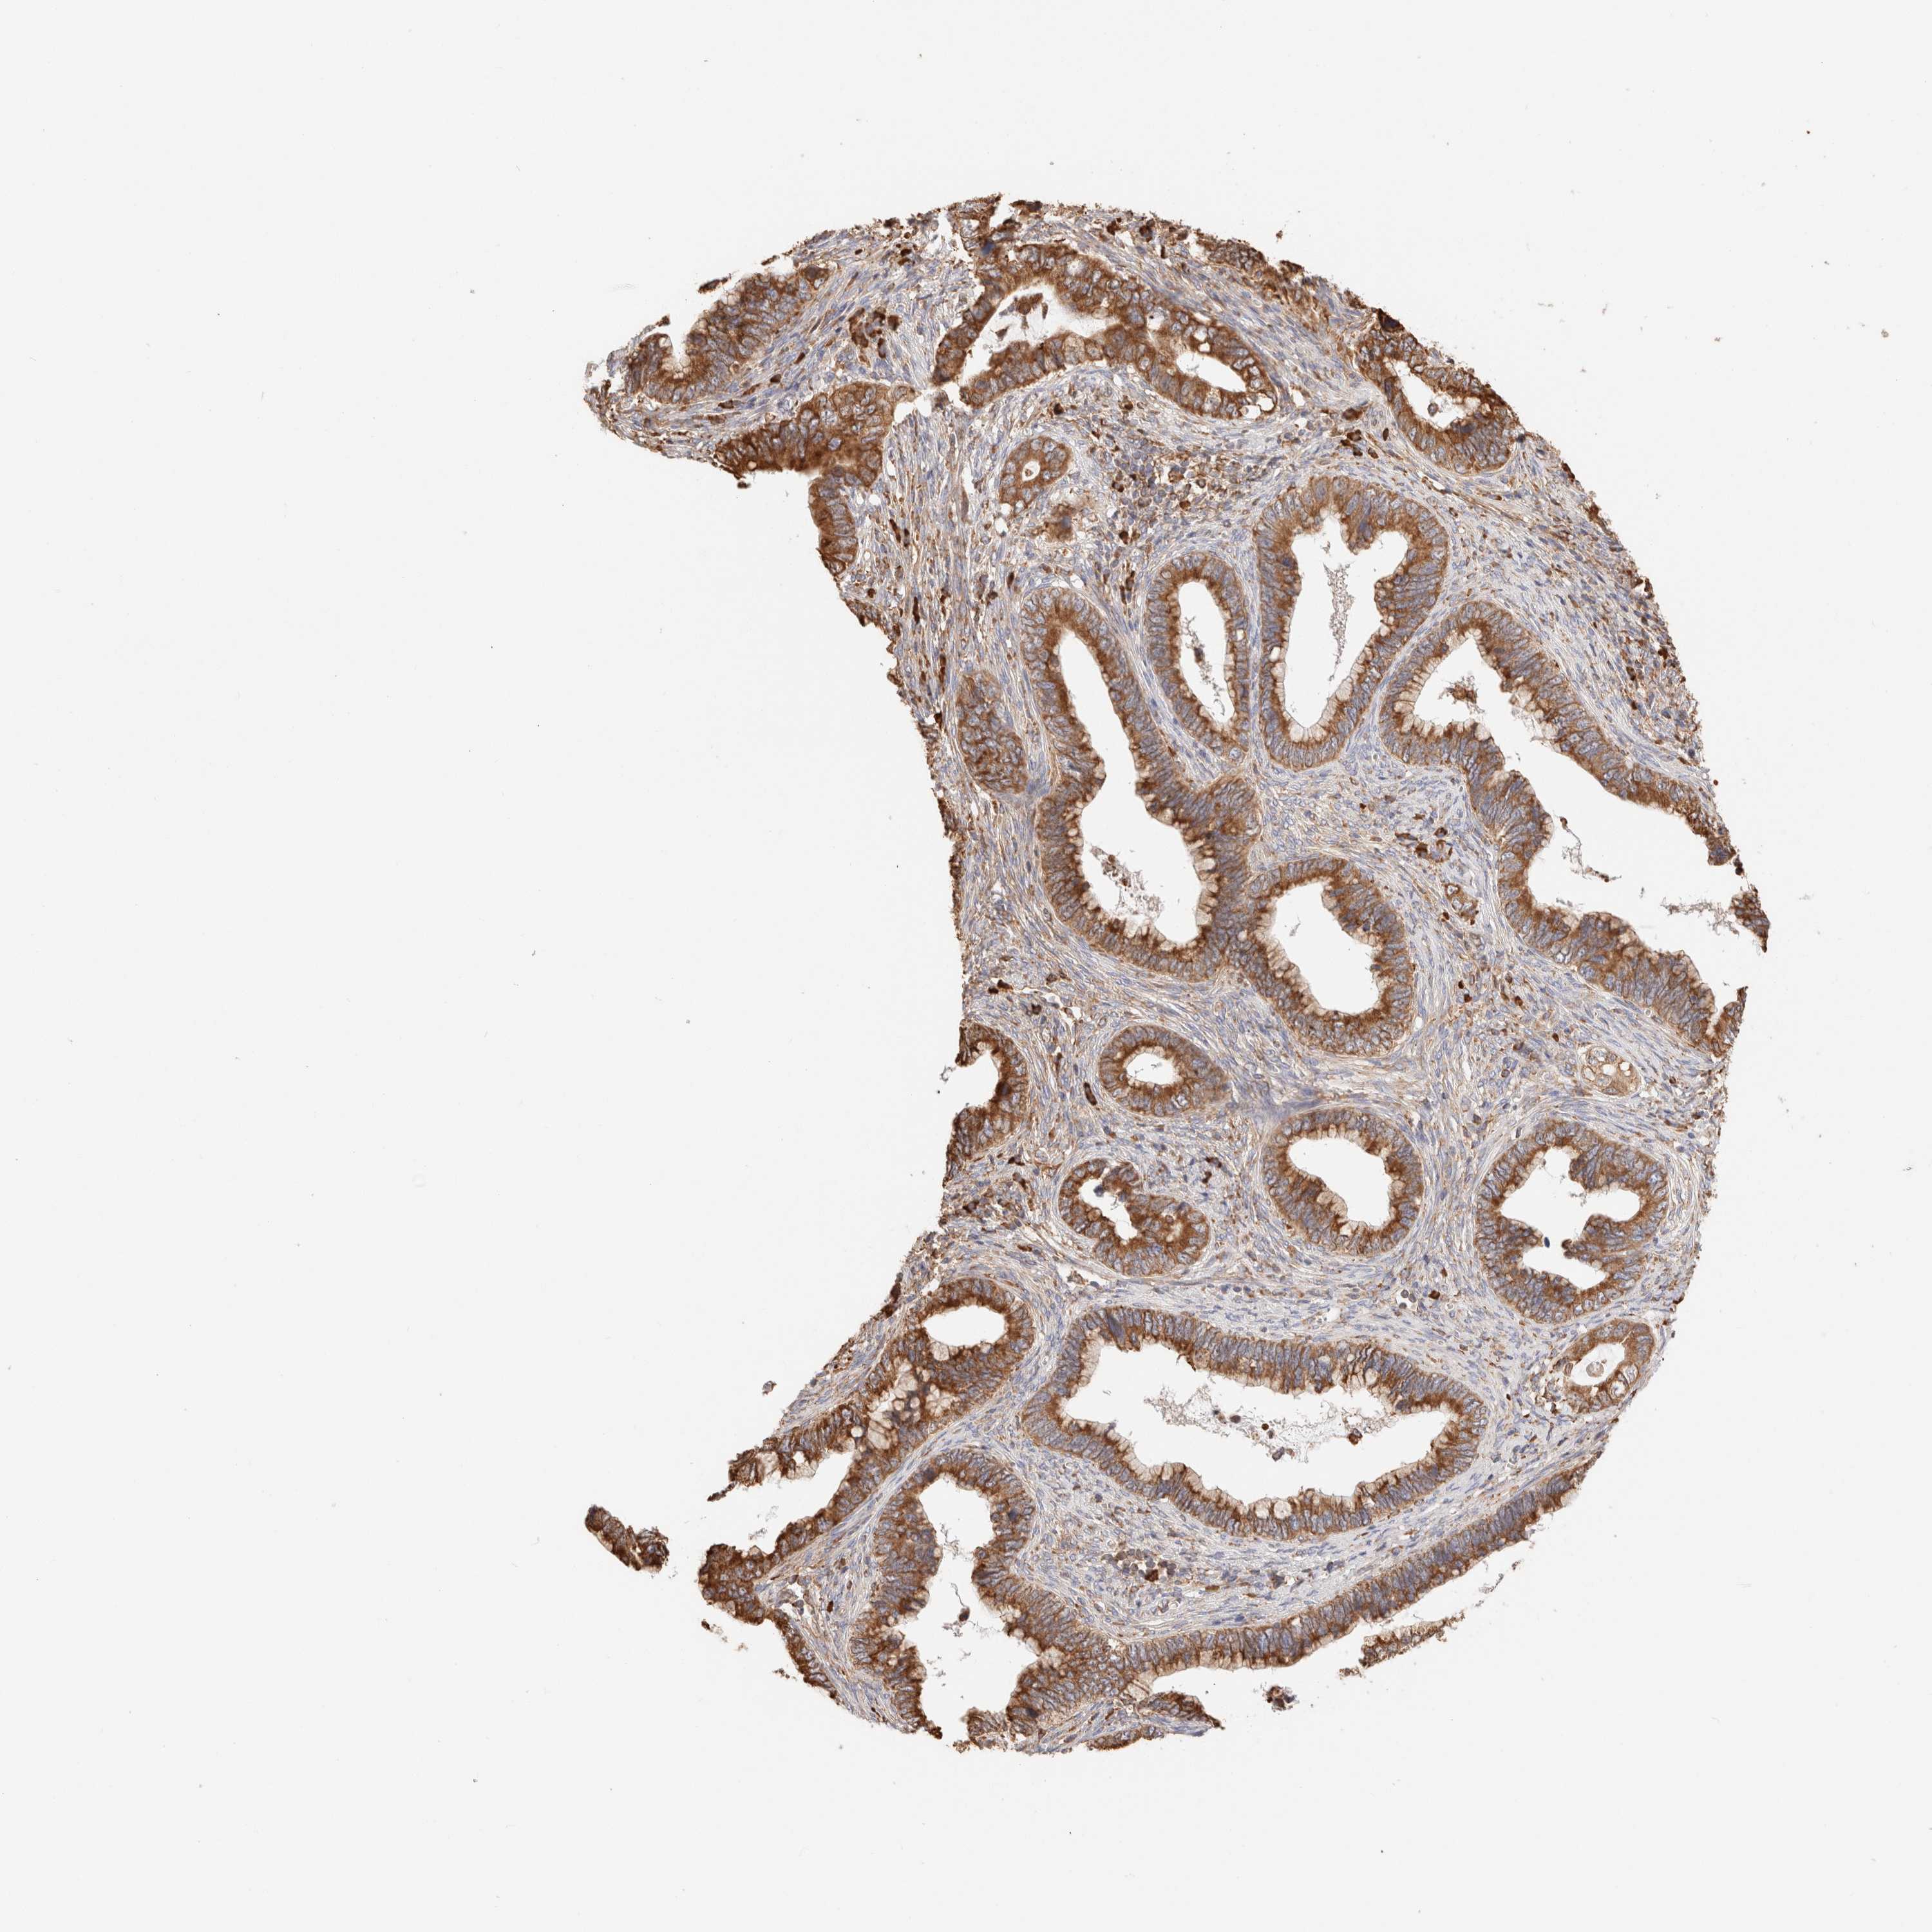

CERVICAL CANCER - Protein expressioni

A mouse-over function shows sample information and annotation data. Click on an image to view it in a full screen mode. Samples can be filtered based on level of antibody staining by selecting one or several of the following categories: high, medium, low and not detected. The assay and annotation is described here.

Note that samples used for immunohistochemistry by the Human Protein Atlas do not correspond to samples in the TCGA dataset.

Antibody stainingi

Antibody staining in the annotated cell types in the current human tissue is reported as not detected, low, medium, or high, based on conventional immunohistochemistry profiling in selected tissues. This score is based on the combination of the staining intensity and fraction of stained cells.

Each image is clickable and will lead to virtual microscopy that enables deeper exploration of all samples and also displays staining intensity scores, fraction scores and subcellular localization as well as patient and tissue information for each sample.

Antibody HPA007641

Antibody CAB022464

Squamous cell carcinoma, NOS

Adenocarcinoma, NOS